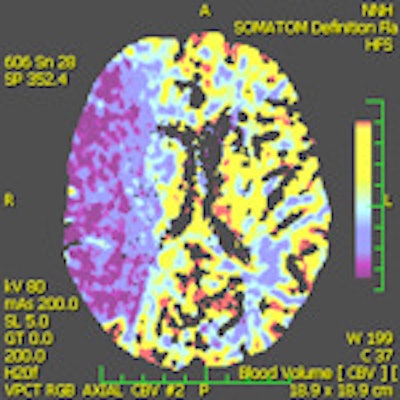

A 28-year-old male with a history of aortic valve replacement and poor compliance with anticoagulative medication, presented with sudden left-sided hemiplegia. No penumbra was apparent on perfusion CT, as shown in left figure (CBF) and middle figure (CBV). Standard CT image (right figure) two days following decompressive craniectomy shows significant mass effect with dislocation of midline structures. Images courtesy of Dr. Josef Vymazel.When ultrafast CT scanners covering almost the entire brain are used, the potential to detect ischemia and salvageable tissue is very similar to MRI. However, the major drawback of CT is the high radiation dose, while in MRI it is the more complicated and time-consuming aspect of the examination, he wrote in an article published online on 29 September by Insights into Imaging.

"The introduction of perfusion CT (PCT) of the brain has significantly improved the sensitivity and specificity in detecting fresh ischemia. Perfusion deficit can be detected immediately after stroke, i.e., in the time when a standard CT is still negative," Vymazal stated.

Different parameters are used in routine clinical practice for the detection of penumbra with CT and MRI. The subtraction of cerebral blood flow (CBF) and cerebral blood volume (CBV) is the usual way to detect penumbra using CT, according to the authors. On MRI, a subtraction between perfusion parameters (mean transit time, time to peak, or CBF) and diffusion-weighted imaging, rather than CBV, is used because CBV (especially on MRI) is not sensitive enough to detect small lesions. Such lesions are easily detected with DWI, according to the authors. DWI, on the other hand, may underestimate the final stroke volume and grows into CBV over the time.